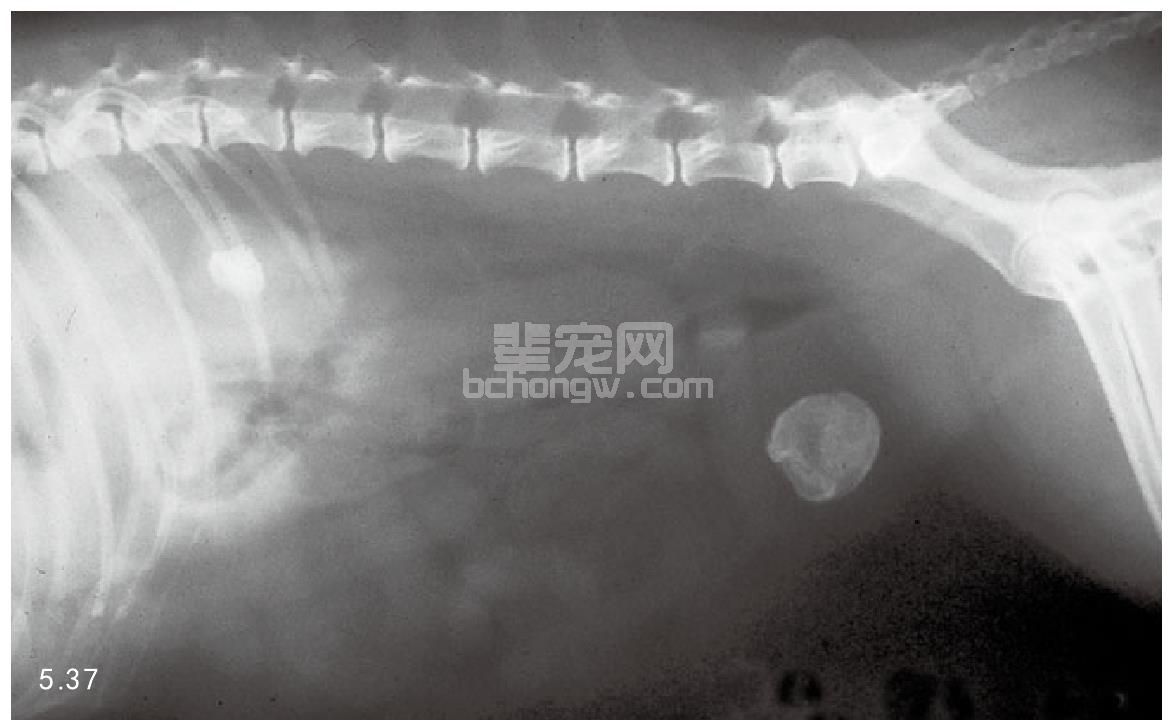

犬の膀胱結石とは、尿をためる袋とも言うべき膀胱に結石を生じた状態を言います。 膀胱 (ぼうこう)とは腎臓から送られてくる尿を一時的に溜める袋状の器官であり、左右の腎臓から尿管を通して尿を受け取り、尿道を通して体外に排出します。 膀胱結石は尿路結石の中で最も発症頻度が高く、多くは 膀胱炎 に引き続いて起こります。 尿道が短くて細菌の進入. うえの犬猫病院は犬 リンク 採用情報 お問合せ 症例紹介 膀胱結石 膀胱結石とは 膀胱結石は膀胱炎や細菌感染、尿路閉塞の原因になります。特に尿路閉塞が危険で、結石が排尿路に詰まると急性腎不. Case42 膀胱結石の犬の1例 血尿と頻尿を主訴に来院した8歳の雄のワンちゃんです。 4ヶ月前にも同様の症状がありましたが抗生剤の投与で改善しました。 今回も同様の治療を試みましたが間欠的に血尿が続き、再発ということもありレントゲンと超音波検査を実施しました。 レントゲン検査では膀胱領域に数ミリの結石を認め、超音波検査でも複数の結石が確認され.

犬 膀胱結石・尿道結石 チワワ 10歳11ヶ月齢 去勢オス 71kg 頻尿と血尿、排尿障害を主訴に来院 腹部と陰茎の触診検査にて結石症が疑われたため、 レントゲン検査を行い、膀胱結石および尿道結石、腎臓結石と診断した 尿道内にぎっしりとつまった結石は、カテーテルにて膀胱内に押し戻し、膀胱切開にて膀胱結石を摘出した 腎臓結石はに対する外科処置は、腎臓. 犬の膀胱結石 更新日時: ミニチュアダックスフンド、オス (去勢)、11歳 《主訴》血尿、排尿しづらい (少量ずつしか出ない) 《検査》①腹部レントゲン検査 膀胱に結石と思われる不透過性陰影を多数確認 ②腹部超音波検査 膀胱内に結石と思われるシャドーを引く高エコー物を多数確認 ③尿.

一例犬膀胱结石诊疗报告

一例犬膀胱结石的诊断与治疗